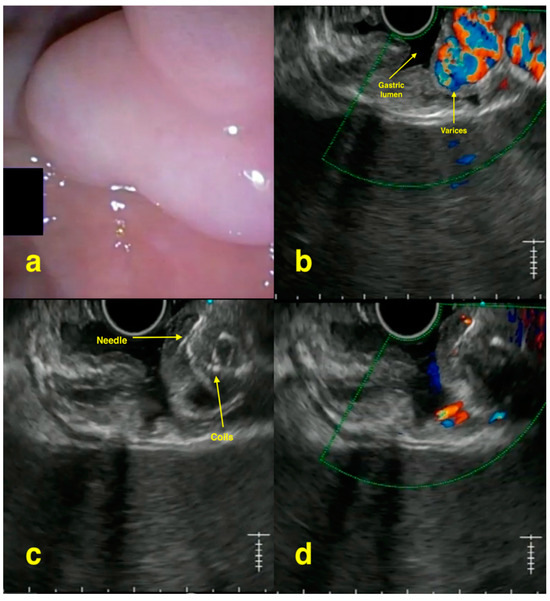

2. EUS-Guided Treatment of Gastric Varices

- Chavan, R.; Baraldo, S.; Patel, N.; Gandhi, C.; Rajput, S. Technical tips for EUS-guided embolization of varices and pseudoaneurysms. VideoGIE 2023, 9, 211–219. [Google Scholar] [CrossRef] [PubMed] [PubMed Central]